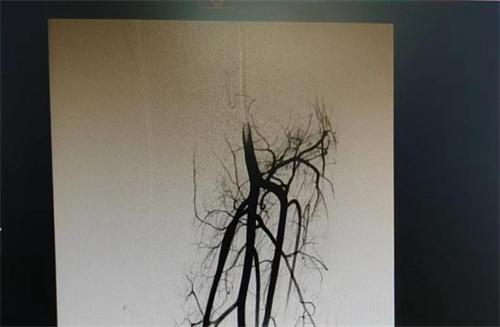

因為7歲的女孩出生的時候身上就有紅斑,當時以為是胎記,但伴隨著不斷的長大,胎記上皮膚溫度越來越高,孩子還有雙腿長短粗細不一樣的癥狀出現。輾轉動的地方就醫之后,武漢兒童醫院,最終確診這位女童患有血管罕見病,腿部血管有著多發性的畸形,經微創介入手術之后,利用德巴斯基的導管,將雜亂無章的血管封堵好,有著明顯的好轉現象。

在下肢做完磁共振和血管造影等檢查之后,發現左腿血管多處都有畸形動脈,靜脈之間有較為異常連接的通道,一部分血液循環過程中較為偷懶,走了一條捷徑,使得各個組織之間在營養供給上是很不均衡的。目前這個病重不能夠完全治愈,但可以控制病情發展縮小差異。